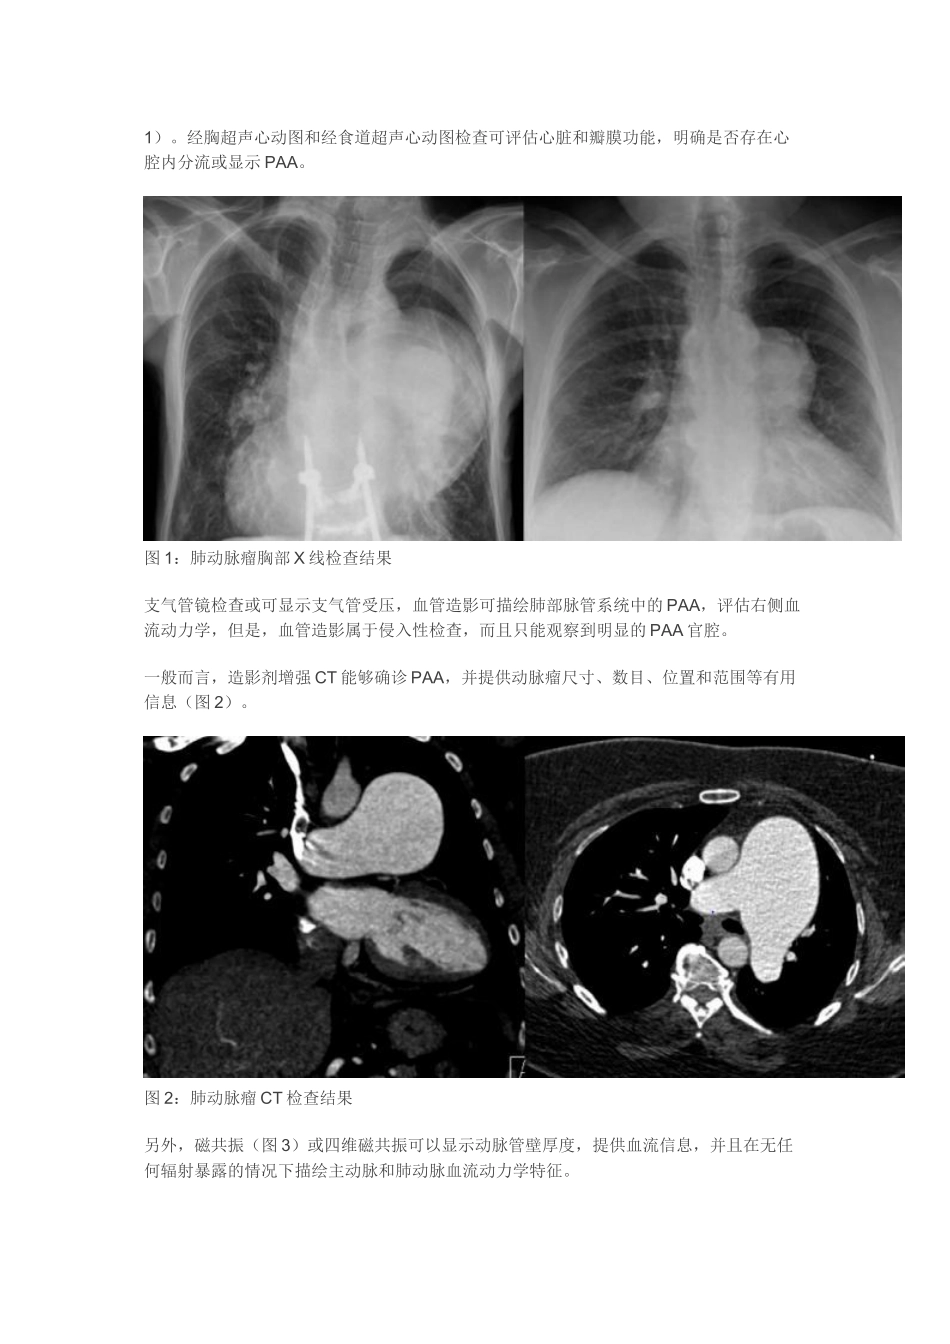

临床综述:肺动脉瘤诊断和治疗来源:丁香园作者:iang肺动脉瘤(PAA)罕见,且较少确诊。PAA与主动脉瘤相比,发病年龄较轻,但性别无差异。89%的PAA位于肺动脉干,仅有11%位于肺动脉分支,累及左肺动脉较右肺动脉更为常见。近期,德国弗莱堡大学的Kreibich博士等在Circulation杂志上发表了一篇关于肺动脉瘤的综述,对其病因、临床表现、诊断和治疗进行了阐述。一、定义目前PAA尚无统一定义。CT成像中成人肺动脉干最大直径为29mm,因此,有学者将PAA定义为肺动脉局部扩张超过最大正常直径。但是,也有学者认为肺动脉直径超过40mm才定义为PAA,以区别肺动脉扩张和真PAA。二、病因肺动脉瘤病因主要分为三方面:先天性、后天性和特发性。1、先天性病因先天性病因是PAA最为主要的病因,超过50%PAA与先天性心脏病有关。三种最为常见引起PAA的先天性心脏病依次为动脉导管未闭、室间隔缺损和房间隔缺损,主要是由于左向右分流增加肺动脉血流管壁应力,导致动脉瘤形成。主动脉瓣发育不良和二叶主动脉瓣等主动脉瓣病变以及肺动脉瓣狭窄、肺动脉瓣返流和肺动脉瓣缺如等肺动脉瓣病变均与PAA相关。其它导致血管壁缺陷和血管壁异常的疾病,如Ehlers-Danlos综合征、马凡综合征和囊性中央坏死等,均可能导致PAA。2、后天性病因(1)感染性疾病过去,导致PAA最为常见的感染性疾病为梅毒和肺结核。进展期梅毒患者PAA形成往往位于直径较大的肺动脉,而进展期肺结核患者易在肺实质间形成PAA。如今,化脓性细菌感染越来越多见于肺动脉假性动脉瘤形成。另外,感染性心内膜炎形成的脓毒性栓塞和真菌性肺炎也可能导致PAA。(2)血管炎以口腔和生殖器反复溃疡以及葡萄膜炎为特征的白塞斯综合征是一种慢性多系统血管炎,其可能导致PAA形成,典型累及血管为右肺下叶动脉,伴反复血栓形成和周围炎症。另外,Hughes-Stovin综合征,一种发生于青年男性的罕见自身免疫性疾病,也可能导致PAA形成,反复血栓性静脉炎和PAA破裂。(3)肺动脉高压和慢性肺动脉栓塞肺动脉高压(PAH)是PAA形成重要原因之一,也是PAA的临床表现之一。事实上,PAA有助于诊断PAH,而且PAA是PAH可靠指标之一。慢性肺动脉栓塞也是一种PAA相对常见的病因,慢性肺动脉栓塞导致的PAA瘤壁较薄或壁内血栓形成钙化。(4)肿瘤原发性肺部肿瘤和肺部转移瘤可侵蚀肺动脉,导致假性动脉瘤形成。另外,平滑肌肉瘤和血管肉瘤等源于肺动脉的原发性肿瘤可导致肺动脉管壁瘤样扩张。(5)医源性心脏外科手术、导管、胸腔引流管、血管造影、手术切除和组织活检均可能导致PAA形成3、特发性病因特发性PAA较为罕见,但文献报道趋于增多。关于特发性PAA的诊断标准,有学者提出4条病理标准:肺动脉干单一扩张伴或不伴其余肺动脉分支扩张,无心脏内或心脏外分流,无慢性心脏或肺脏疾病以及无动脉炎或肺动脉粥样硬化。三、临床表现一般而言,PAA临床表现无特异性,大多数PAA患者,即使PAA直径达70mm,无明确主诉。PAA常见临床表现包括呼吸困难、胸痛、声音嘶哑、心悸和晕厥发作等。PAA压迫支气管可导致紫绀、咳嗽、呼吸困难加重、肺炎、发热和支气管炎等。另外,PAA患者发生肺栓塞风险较高。PAA也可能出现咯血症状,预示动脉瘤可能即将发生破裂,一旦发生破裂,可能出现窒息和猝死。在所有报道的PAA病例中,三分之一死于动脉瘤破裂,表明并非所有PAA进展至破裂阶段。根据PAA形成病因,患者往往存在右心房和右心室肥厚,右心衰,三尖瓣返流(瓣环扩张所致)以及轻度心包积液和胸腔积液。夹层是PAA罕见但威胁生命的并发症,肺动脉夹层几乎全部发生于出现动脉瘤动脉扩张的肺动脉,最常见发生部位位于肺动脉干(占80%),仅有15%PAA夹层能在存活患者中得到确诊。PAA夹层临床症状包括严重呼吸困难、胸骨后疼痛、中央型紫绀、心源性休克和猝死。PAA夹层导致心包填塞是此类患者的主要死因。四、诊断听诊PAA患者可闻及舒张期杂音。心电图检查可见右心室或右心房肥厚表现,胸部X线检查可见肺门增大、肺部结节或肺部团块,也可见动脉瘤样肺动脉阶段或肺动脉扩张(图1)。经胸超声心动图和经食道超声心动图检查可评估心脏和瓣膜功能,明确是否存在心腔内分流或显示PAA。图1:肺动...